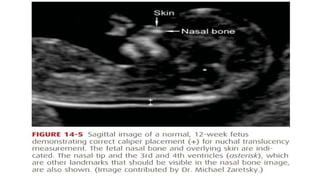

• This is the maximum thickness of the subcutaneous translucent area

between the skin and soft tissue overlying the fetal spine at the back

of the neck

• An increased NT thickness itself is not a fetal abnormality, but rather

is a marker that confers increased risk

• Approximately one third of fetuses with increased nuchal

translucency thickness will have a chromosome abnormality, nearly

half of which are Down syndrome

• Figure 14.5

First-Trimester Screening • Themost commonly used protocol involves measurement of sonographic nuchal translucency and two maternal serum analytes. • This is performed between 11 and 14 weeks’ gestation. • This is the maximum thickness of the subcutaneous translucent area between the skin and soft tissue overlying the fetal spine at the back of the neck • An increased NT thickness itself is not a fetal abnormality, but rather is a marker that confers increased risk • Approximately one third of fetuses with increased nuchal translucency thickness will have a chromosome abnormality, nearly half of which are Down syndrome

• #14 The NT measurement is expressed as a multiple of the gestational age-specific median, similar to serum markers used for aneuploidy screening Increased NT thickness is also associated with other aneuploidies, genetic syndromes, and various birth defects, especially fetal cardiac anomalies (Atzei, 2005; Simpson, 2007). Because of this, if the NT measurement is 3.5 mm or greater, the patient should be offered targeted sonography, with or without fetal echocardiography, in addition to fetal karyotyping The NT must be imaged and measured with a high degree of precision for aneuploidy detection to be accurate. This has led to standardized training, certification, and ongoing quality review programs. In the United States, training, credentialing, and monitoring are available through the Nuchal Translucency Quality Review (NTQR) program (www.ntqr.org)

• #15 It is measured in the sagittal plane, when the crown-rump length measures between 38 and 84 mm. Specific criteria for NT measurement are listed in Table 10-3 (p. 196). As shown in Table 14-5, as an isolated marker, NT detects 64 to 70 percent of fetuses with Down syndrome at a falsepositive rate of 5 percent, and it has maximal sensitivity at 11 weeks (Malone, 2005b). The risk conferred by an increased NT thickness is independent of that of serum analytes, and combining NT with serum analyte values results in greatly improved aneuploidy detection Thus, NT is generally used as an isolated marker only in screening for multifetal gestations, in which serum screening is not as accurate or may not be available (American College of Obstetricians and Gynecologists, 2013c). An exception is that if the NT measurement is increased to 3 to 4 mm, then the aneuploidy risk is unlikely to be normalized using serum analyte assessment, and invasive testing should be offered

• #23 Each has also been associated with an increased risk for trisomies 18 and 13 and other aneuploidies. However, these signs have not become widely adopted for routine use in the United States. Fetal Nasal Bone. In approximately two thirds of fetuses with Down syndrome, the nasal bone is not visible at the 11- to 14-week examination (Cicero, 2004; Rosen, 2007; Sonek, 2006). Currently, this is the only first-trimester marker, other than NT, for which the Nuchal Translucency Quality Review Program has established a training program. Criteria for adequate assessment include that the fetus occupies most of the image; that there be a 45-degree angle of insonation with the fetal profile; that the profile be well defined in the midsagittal plane, with the tip of the nose and the third and fourth ventricles visible; and that the nasal bone brightness be greater than or equal to that of the overlying skin